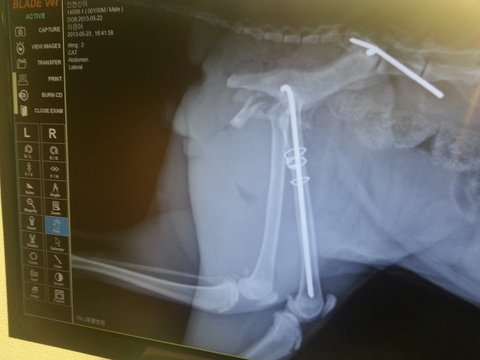

골반골절/대퇴골절 수술후 일주일 사진주의 [신이]

[2013년 5월 21일 인천서구 가좌ic 부근 한신빌리지앞 도로]

교통사고를 당해 대퇴부 및 골반골절로 안락사 판정을 받았고

주인이 없는 길고양이 신이가 할수 있는건 그 아무것도 없었습니다.

수술을 받아도 배변장애와 후지마비의 가능성이 너무나 높았기에 선뜻 수술을

결정할 수도 없었습니다.

그 힘들었던 골절수술과 무척이나 더웠던 올여름 날씨탓에 더더욱 힘들었던 치료과정을 다견디며

버텨준 우리 신이가 후지마비의 가능성을 이겨내고 제눈앞에서 이제 걸어요...아니 뜁니다 ㅠㅠ

턱시도 깜장색 1~2살 / 남아 /중성화 완료/ 골절수술과 재활 경과 모두 정상/